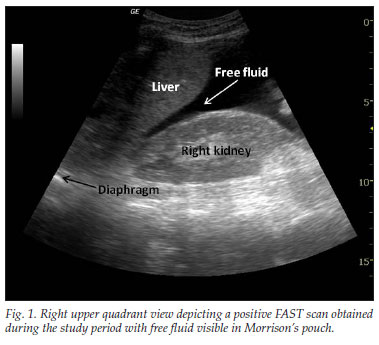

The RUQ is the most sensitive region for free fluid in comparison to the other eFAST views.

The RUQ should be divided into 3 zones.

1. Above/Below the diaphragm,

2. Morrison’s pouch (hepato-renal recess)

3. Para-colic gutter: Around the inferior hepatic edge/inferior pole of kidney

The key is to know your landmarks, and STOP, STAY and widely FAN through each zone well, adjusting your depth as necessary to keep the area of interest centered on your screen.

Start high to stay and fan (anterior to posterior) around the diaphragm. Then, SLIDE down into another rib space, stop, stay and fan around the entire kidney. An additional rib space may be necessary to evaluate the para-colic gutter.

Tips for RUQ Diaphragm View :

The liver may be easily seen, but the diaphragm can be more difficult, especially if it’s behind a rib shadow, inspiration views can help. This lowers the diaphragm into your view and allows visualization of the thoracic cavity for haemothorax/pleural fluid as well as sub-diaphragmatic peritoneal fluid.

Visualization of the spine shadow traveling in the lower part of the screen will normally stop at the diaphragm with a mirror image artifact illustrated in the thoracic cavity. However if the spine is able to be seen above the diaphragm...this is suggestive of pleural fluid